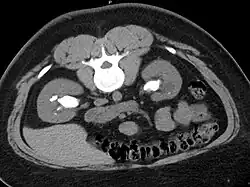

Otherwise a noncontrast helical CT scan with 5 millimeters (0.2 in) sections is the diagnostic method to use to detect kidney stones and confirm the diagnosis of kidney stone disease.[13][47][51][52][7] Near all stones are detectable on CT scans with the exception of those composed of certain drug residues in the urine,[53] such as from indinavir. Calcium-containing stones are relatively radiodense, and they can often be detected by a traditional radiograph of the abdomen that includes the kidneys, ureters, and bladder (KUB film).[53] Some 60% of all renal stones are radiopaque.[51][54] In general, calcium phosphate stones have the greatest density, followed by calcium oxalate and magnesium ammonium phosphate stones. Cystine calculi are only faintly radiodense, while uric acid stones are usually entirely radiolucent.[55]

Bilateral staghorn calculi as seen on CT